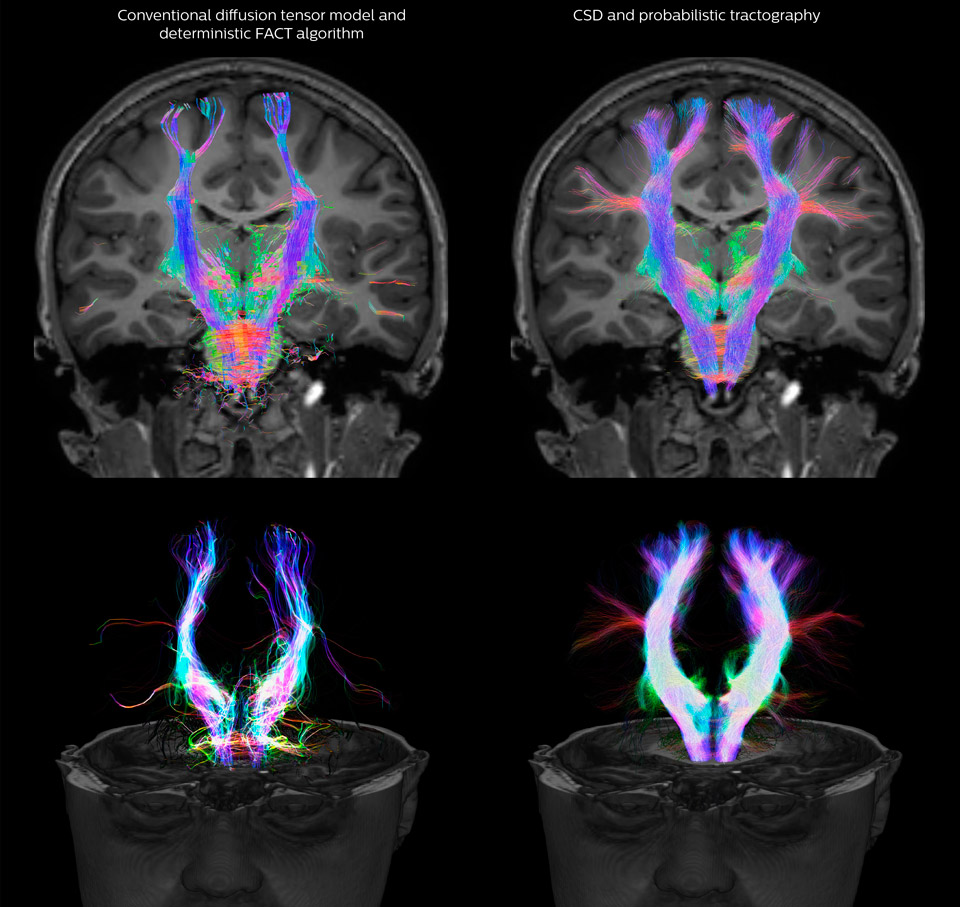

Fiber tractography of the corticospinal tract with seed region of the posterior limb of the internal capsule. Different processing based on the same data.

All images were created from the same acquisition in a child using Ingenia 3.0T CX and 32-channel dS Head coil. Diffusion data was acquired at b-values 0, 500, 1000, 2000, 3000. The use of high b-values (3000 s/mm2) effectively suppresses extra-axonal water signal and provides high angular resolution.

Legend of acronyms

CSD: constrained spherical deconvolution

DEC TDI: directionally encoded color track-density imaging

DTI: diffusion tensor imaging

DWI: diffusion-weighted imaging

FOD: fiber orientation density

Data processing was performed using open source software. Fiber tracking was performed using the MRtrix package (J-D Tournier, Brain Research Institute, Melbourne, Australia, https://github.com/MRtrix3/mrtrix3), Tournier et al. 2012. DEC TDI based on F Calamante et al 2010.